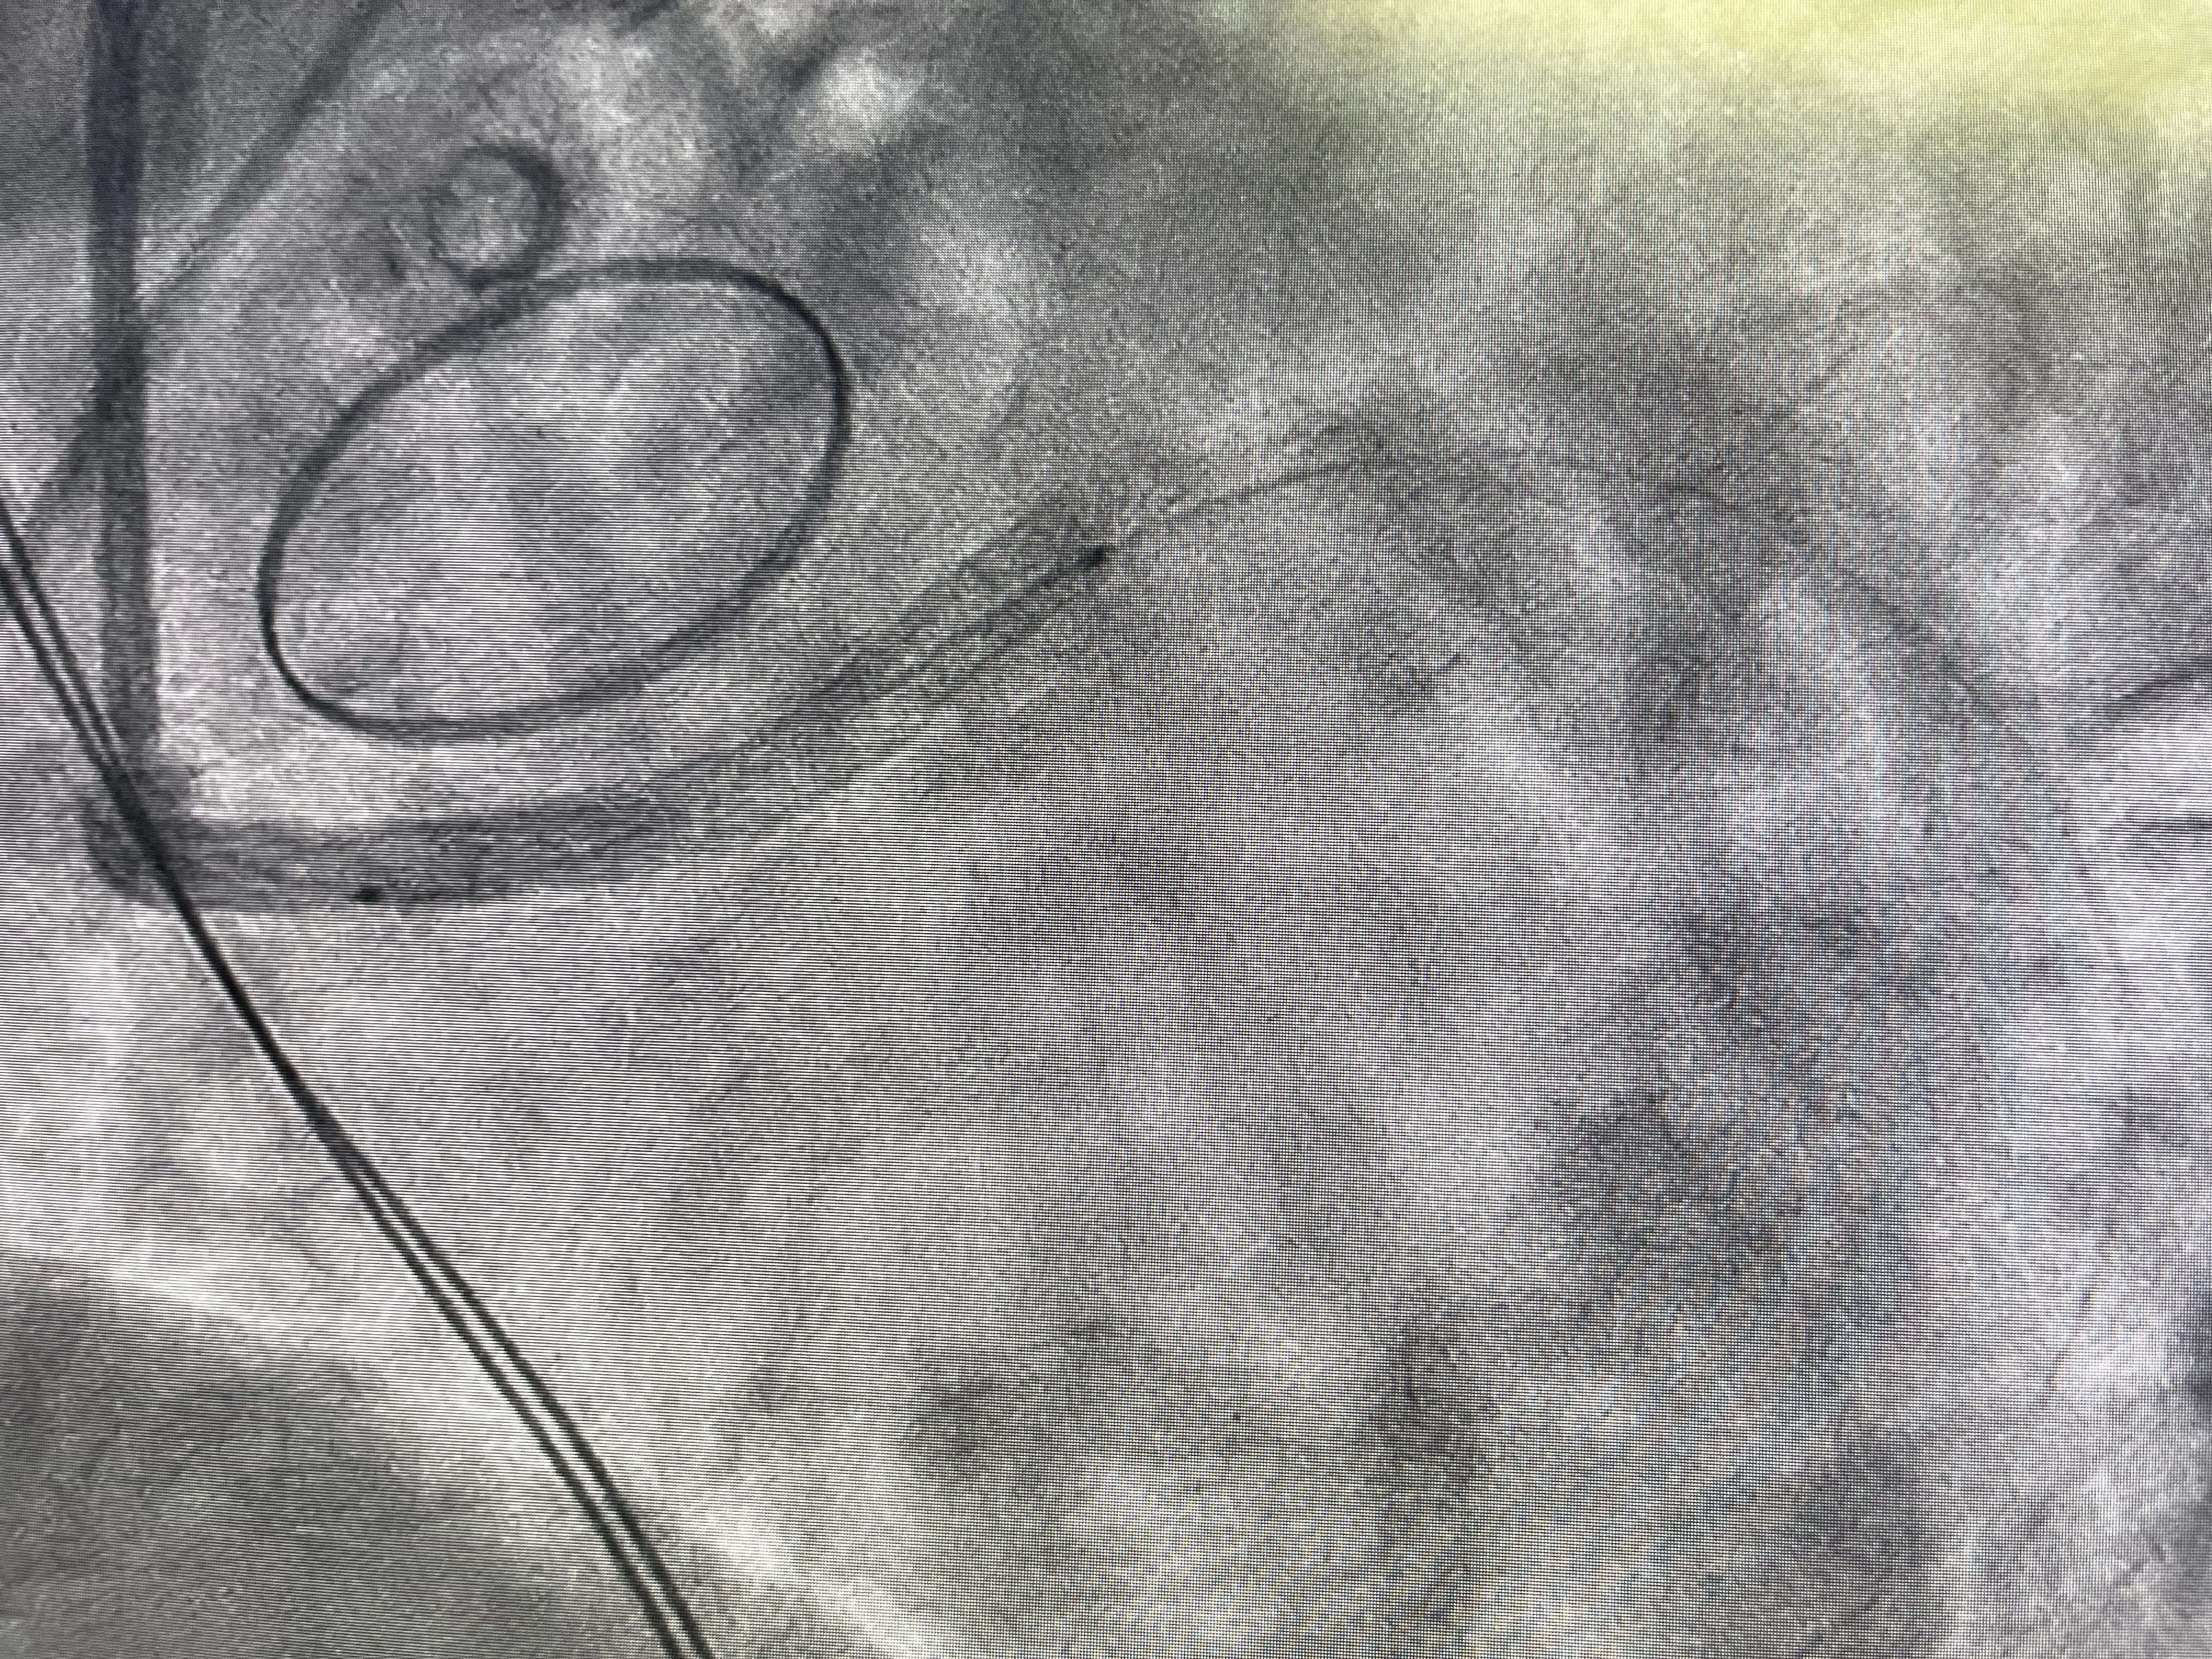

Durante el cateterismo, el objetivo principal es visualizar el árbol coronario y localizar la causa de la elevación del ST. Al inyectar contraste y analizar las imágenes, se hace evidente que la arteria circunfleja está ocluida. La sorpresa, aunque coherente con la anatomía conocida, es que la oclusión no se debe a una placa aterosclerótica inestable, sino a la propia sutura de la válvula mecánica. En otras palabras, la circunfleja ha sido literalmente suturada y estrangulada durante la fijación de la prótesis valvular.

Este hallazgo explica de forma directa el infarto en territorio inferior y la inestabilidad hemodinámica del paciente. El flujo coronario hacia la zona irrigada por la circunfleja está comprometido de forma crítica, generando isquemia severa. En ese momento, el reto del equipo de hemodinámica es doble: por un lado, confirmar que la causa es mecánica y, por otro, intentar restablecer el flujo a pesar de la presencia de la válvula mecánica. No se trata de una angioplastia convencional, sino de una situación límite condicionada por una complicación quirúrgica.

Predilatación y Colocación de Stent

Una vez identificada la oclusión de la circunfleja, el siguiente paso es intentar abrir la arteria con un balón. Se realiza una predilatación cuidadosa, avanzando un balón a través de la zona donde la arteria ha quedado comprometida por la sutura de la válvula mecánica. Esta maniobra busca crear un lumen mínimo que permita restablecer parcialmente el flujo y valorar la respuesta del territorio distal. Es un momento crítico, porque se está actuando en una zona anatómicamente compleja y recientemente manipulada quirúrgicamente.